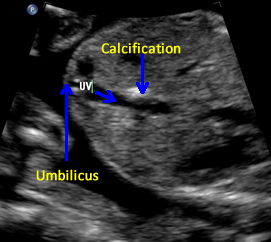

Above. Hepatic calcifications may be within the liver parenchyma itself or may be attached to the liver capsule from conditions such as meconium peritonitis. Calcifications within the liver substance suggest a systemic etiology, such as fetal infections from toxoplasmosis, varicella, CMV, parvovirus, or herpes simplex.

Above. Gestational age is 36 6/7 weeks. Confirmed meconium peritonitis. Note calcifications on capsular surface of the liver, which is the most common cause of the presence of such calcifications.

Above. Gestational age is 23 weeks. Isolated hepatic calcification.

Above. Gestational age is 23 weeks. Isolated hepatic calcification. The calcification measures 4.2 x 7.4 x 6.9 mm. It is adjacent to the hepatic vein.